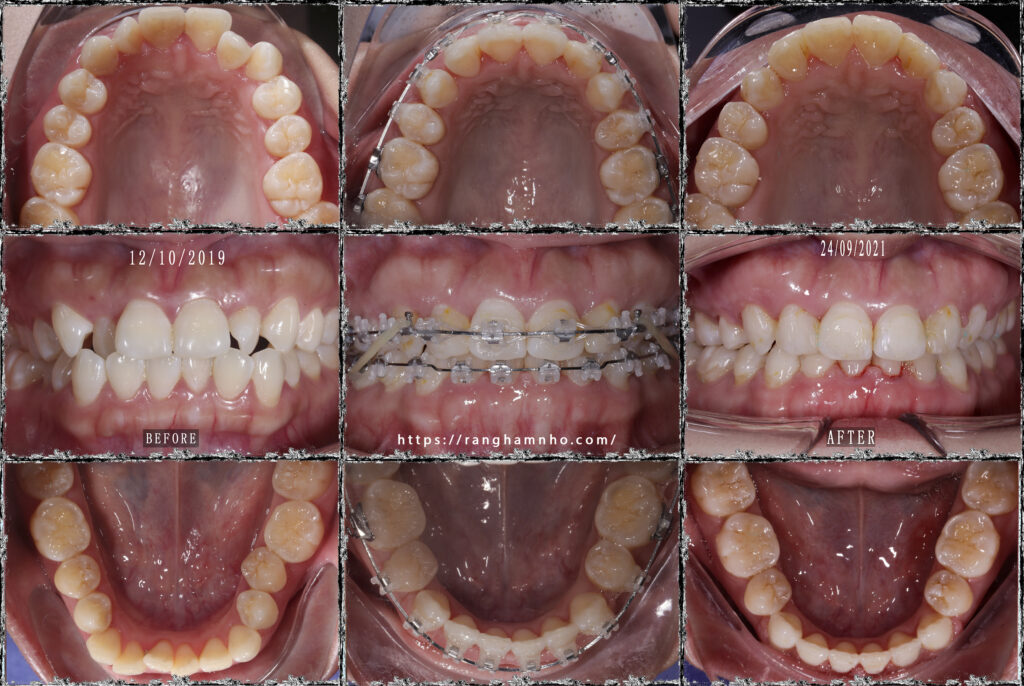

BN chọn niềng mắc cài thẩm mỹ tự buộc- saphirre tự buộc của mỹ, kết quả sau 1.5 năm niềng được tháo với nụ cười và khuôn mặt thay đổi nhiều sau niềng.

Tháo niềng và tiếp tục đeo hàm duy trì ban đêm.